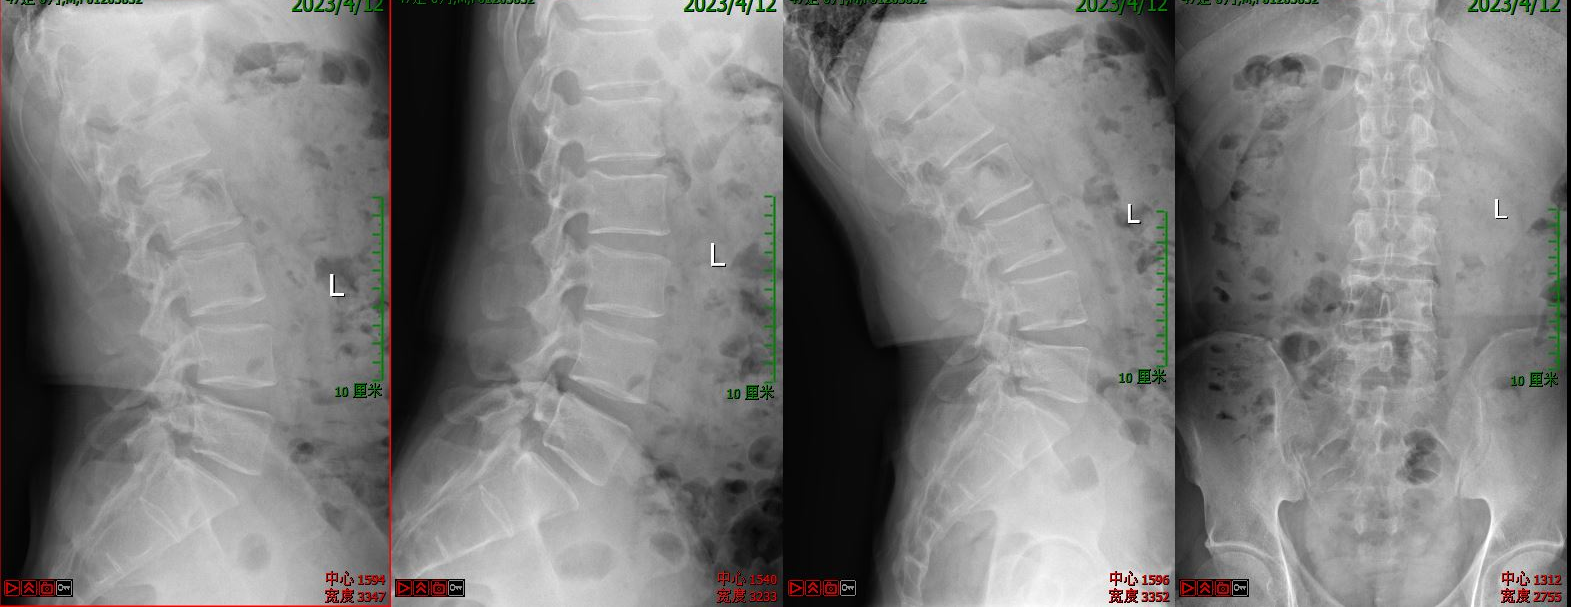

第一例病例为一名中年男性,腰4/5椎间盘突脱出并向下游离接近腰5/骶1椎间隙,为其实施VBE内镜下突出髓核单纯摘除术。患者术前腰痛伴右下肢疼痛麻木1个月余,右拇指背伸肌力明显下降。术后疼痛完全缓解,肌力较前部分恢复,有轻度麻木。

术前X线

术前CT

术前核磁